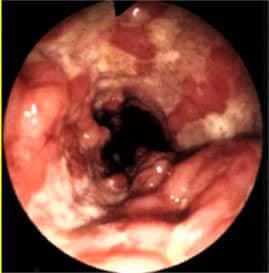

Esas tanı kalın bağırsağın kolonoskopi (ucunda ışık bulunan kameralı bükülebilir, ince bir aletle kalın bağırsakların incelenmesi) ile doğrudan incelenmesi ve hastalıklı dokudan parça alınıp mikroskop altında bakılması ile konur. Hekim gerekli gördüğünde baryumlu grafiler de isteyebilir.